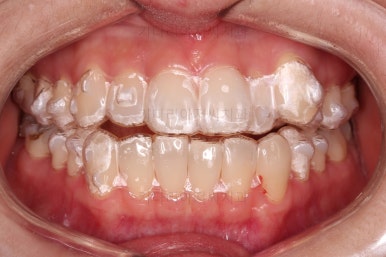

장치를 착용한 사진입니다.

투명한 플라스틱 시트가 치아를 감싸면서 미세하게 움직이는 힘을 주는 장치인데요.

조금 더 투명하게 보이는 팁을 드리자면 내면을 물로 적셔서 착용하게 되면 장치와 치아 사이가 더 밀착하는 느낌을 주며 굉장히 더 투명해 보입니다.

장치를 착용한 얼굴모습인데요.

흐닣 상상하는 교정장치의 느낌과는 다르죠?

장치를 착용했음에도 거의 눈에 띄지 않고요.

(물론 자세히 보면 자연치아와 다른 약간의 이질감은 있긴 있습니다.)

플라스틱 시트가 부피감이 거의 없기 때문에 장치를 착용했다고 입이 더 나와보이는 것도 아닙니다.